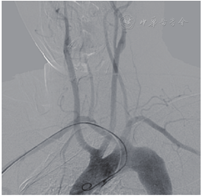

实验室检查提示炎症反应指标高:红细胞沉降率63 mm/h,淀粉样蛋白67.8 mg/L,而其余生化指标正常。脑动脉造影证实双颈总动脉共干,右锁骨下动脉直接起自于主动脉弓(图1)。同时发现患者左侧大脑中动脉慢性闭塞并伴局部新生血管形成(图2)。

结合外院MRI检查,病变性质考虑为桥脑急性梗死。结合本院DSA检查考虑:迷走右锁骨下动脉、右侧大脑中动脉重度狭窄。因此,最终诊断:脑梗死、白塞病、迷走右锁骨下动脉、右侧大脑中动脉重度狭窄。